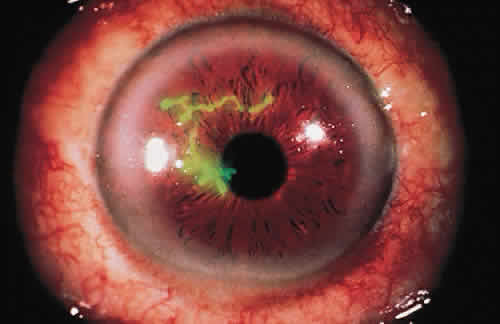

For the factors of innate immunity to be available at the site of potential infection, the factors must be brought to the area of interest through the bloodstream. The acute inflammatory response to bacteria or tissue injury is characterized by capillary dilation and increased capillary permeability. This transfers to the conjunctival epithelium the neutrophils, which play a crucial role in the defense against pyogenic bacteria, such as pneumococci and streptococci. In addition to furthering the transfer of leukocytes, the increased capillary permeability brings about a massive transudation of bactericidal factors contained in the serum: C-reactive protein, defensins, properdin, and the complement system (Fig. 1). These factors aid in the adherence of bacteria to the polymorphonuclear leukocyte and ultimately in phagocytosis.2 Defensins, for example, are considered to be one of the earliest peptide effectors of innate immunity.15 They are released by neutrophils and are present in tears and in the ocular mucosa.16 Defensins have antimicrobial activity against gram-positive and gram-negative bacteria, fungi, and viruses and accelerate wound healing by their mitogenic effect on epithelial cells and fibroblasts.